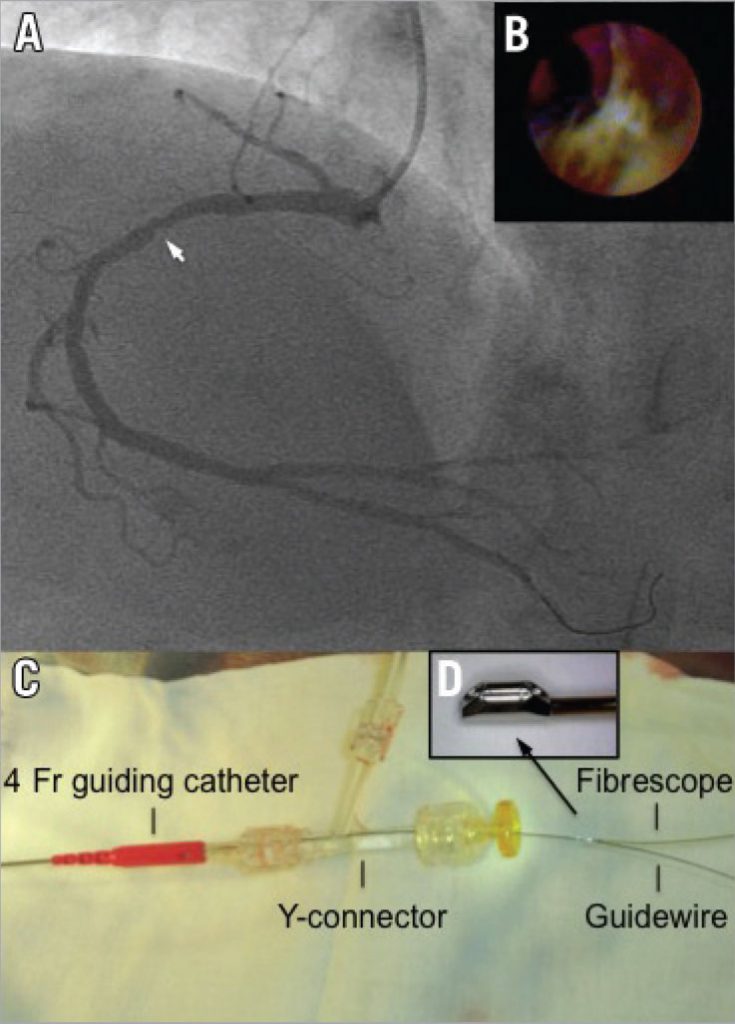

Angioscopy procedure (right anterior oblique cranial view). Fluoroscopy ...

Figure 2 from Retrograde-angioscopy guided wiring technique in chronic ...

Figure 1 from Retrograde-angioscopy guided wiring technique in chronic ...